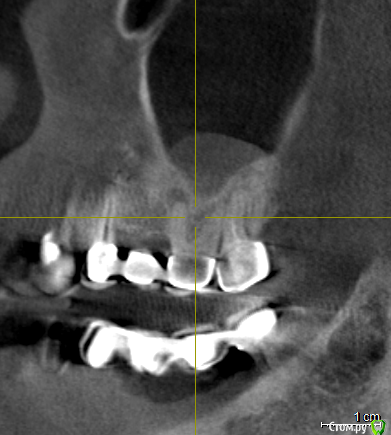

vpaoli Опубликовано 29 февраля, 2016 Поделиться Опубликовано 29 февраля, 2016 (изменено) Посыпались зубы... , что говорят имплантологи-хирурги известно - все удалить и заменить. Хотелось бы получить мнение терапевтов.Под вопросом зубы 16-17, 26-27 и 47. С 45-47 слетел мост, 26-27 после чистки ниткой, у нитки гнилостный запах, над ними в гайморовой пазухе большая киста (видимо как говорят стоматологи онтодогенного происхождения). 47 сидит очень крепко, красноватого цвета, видимо резорцированный и хрупкий. подскажите, можно ли хоть какой то из них лечить?Еще вопрос - над 26, 27 киста в гайморовой пазухе, это опасно или лучше не трогать ? О кисте я узнал только сделав КТ, ранее и сейчас даже не ощущаю ее присутствие.Всех заранее благодарю за высказанное мнение. Изменено 29 февраля, 2016 пользователем vpaoli Ссылка на комментарий

DmitrySH Опубликовано 29 февраля, 2016 Поделиться Опубликовано 29 февраля, 2016 Лучше выложите ссылку на КТ целиком. По данным скриншотам верхние лечить, а нижний 50/50 1 Ссылка на комментарий

faity Опубликовано 1 марта, 2016 Поделиться Опубликовано 1 марта, 2016 Если по этим срезам смотреть, то я бы 1.8, 1.6, 4.5 удалил, остальные лечить 2 Ссылка на комментарий

DmitrySH Опубликовано 1 марта, 2016 Поделиться Опубликовано 1 марта, 2016 Что-то КТ скачалось, но при установке ошибку выдает. По этим скринам, 45 точно удаляется. Это без вариантов. У меня есть некоторые сомнения в 4716 да, возможно удаление, но ракурс не очень удачный. ради него и хотел КТ посмотреть.18. не будет функционировать как зуб.Про мост 47-44 лучше сразу забыть и планировать имплантацию в обл 46, 45. 1 Ссылка на комментарий